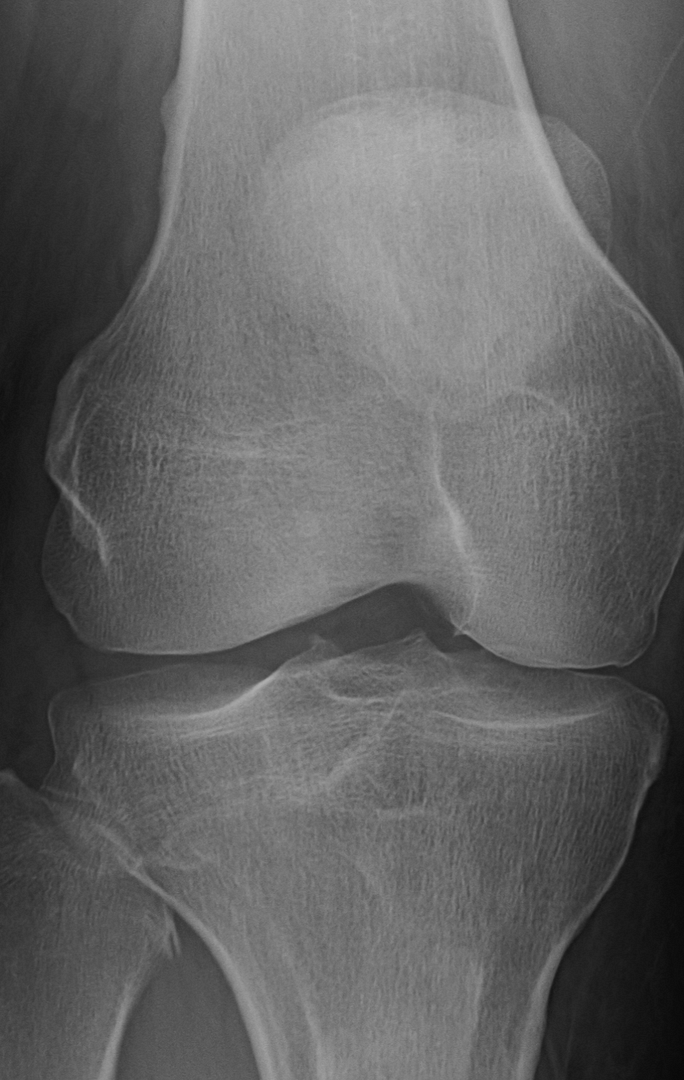

Your sunrise pateler views (bottom knee cap floating in space view) are worrying. You are developing bone avulsions (the part where it looks like it is separating) most likely due to impact injury coupled with straining tendons. You got to start wearing knee pads for what ever you are doing that is impacting them. If that continues in the same path, even walking will be a chore.

On the lateral view I can see see a section of calcification on the anterior aspect. ................... The worrying part is just bellow the calcium I see a region that looks like a chip fracture or an older one. Its the diagonal line with the offset. Of course, I could just be nitpicking and just seeing something that is an optical illusion.